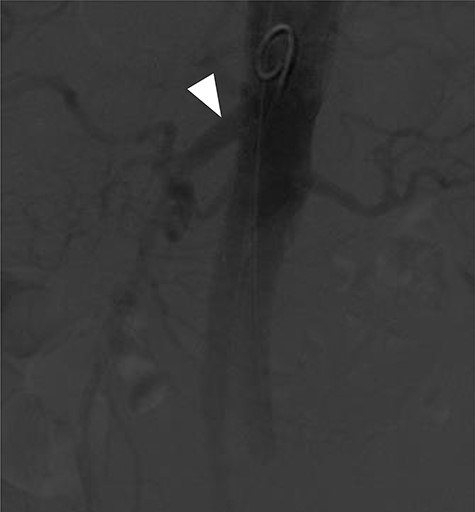

A 78-year-old gentleman admitted for elective FEVAR to treat his CT confirmed 5.7 cm juxtarenal AAA. He was not suitable for open repair and initially offered the option of no intervention due to ongoing comorbidities resulting in poor cardiopulmonary function; however, he was keen to proceed with surgery. From pre-implant planning CT angiogram (CTA), infrarenal endograft was unsuitable for EVAR due to reverse conicity and unhealthy infrarenal aortic neck (Fig. 1); therefore, FEVAR was chosen. RRHA from SMA was also seen in pre-operative CTA but not reported (Fig. 2).

Pre-operative CTA showing healthy SMA (arrowhead) with RRHA (arrow).